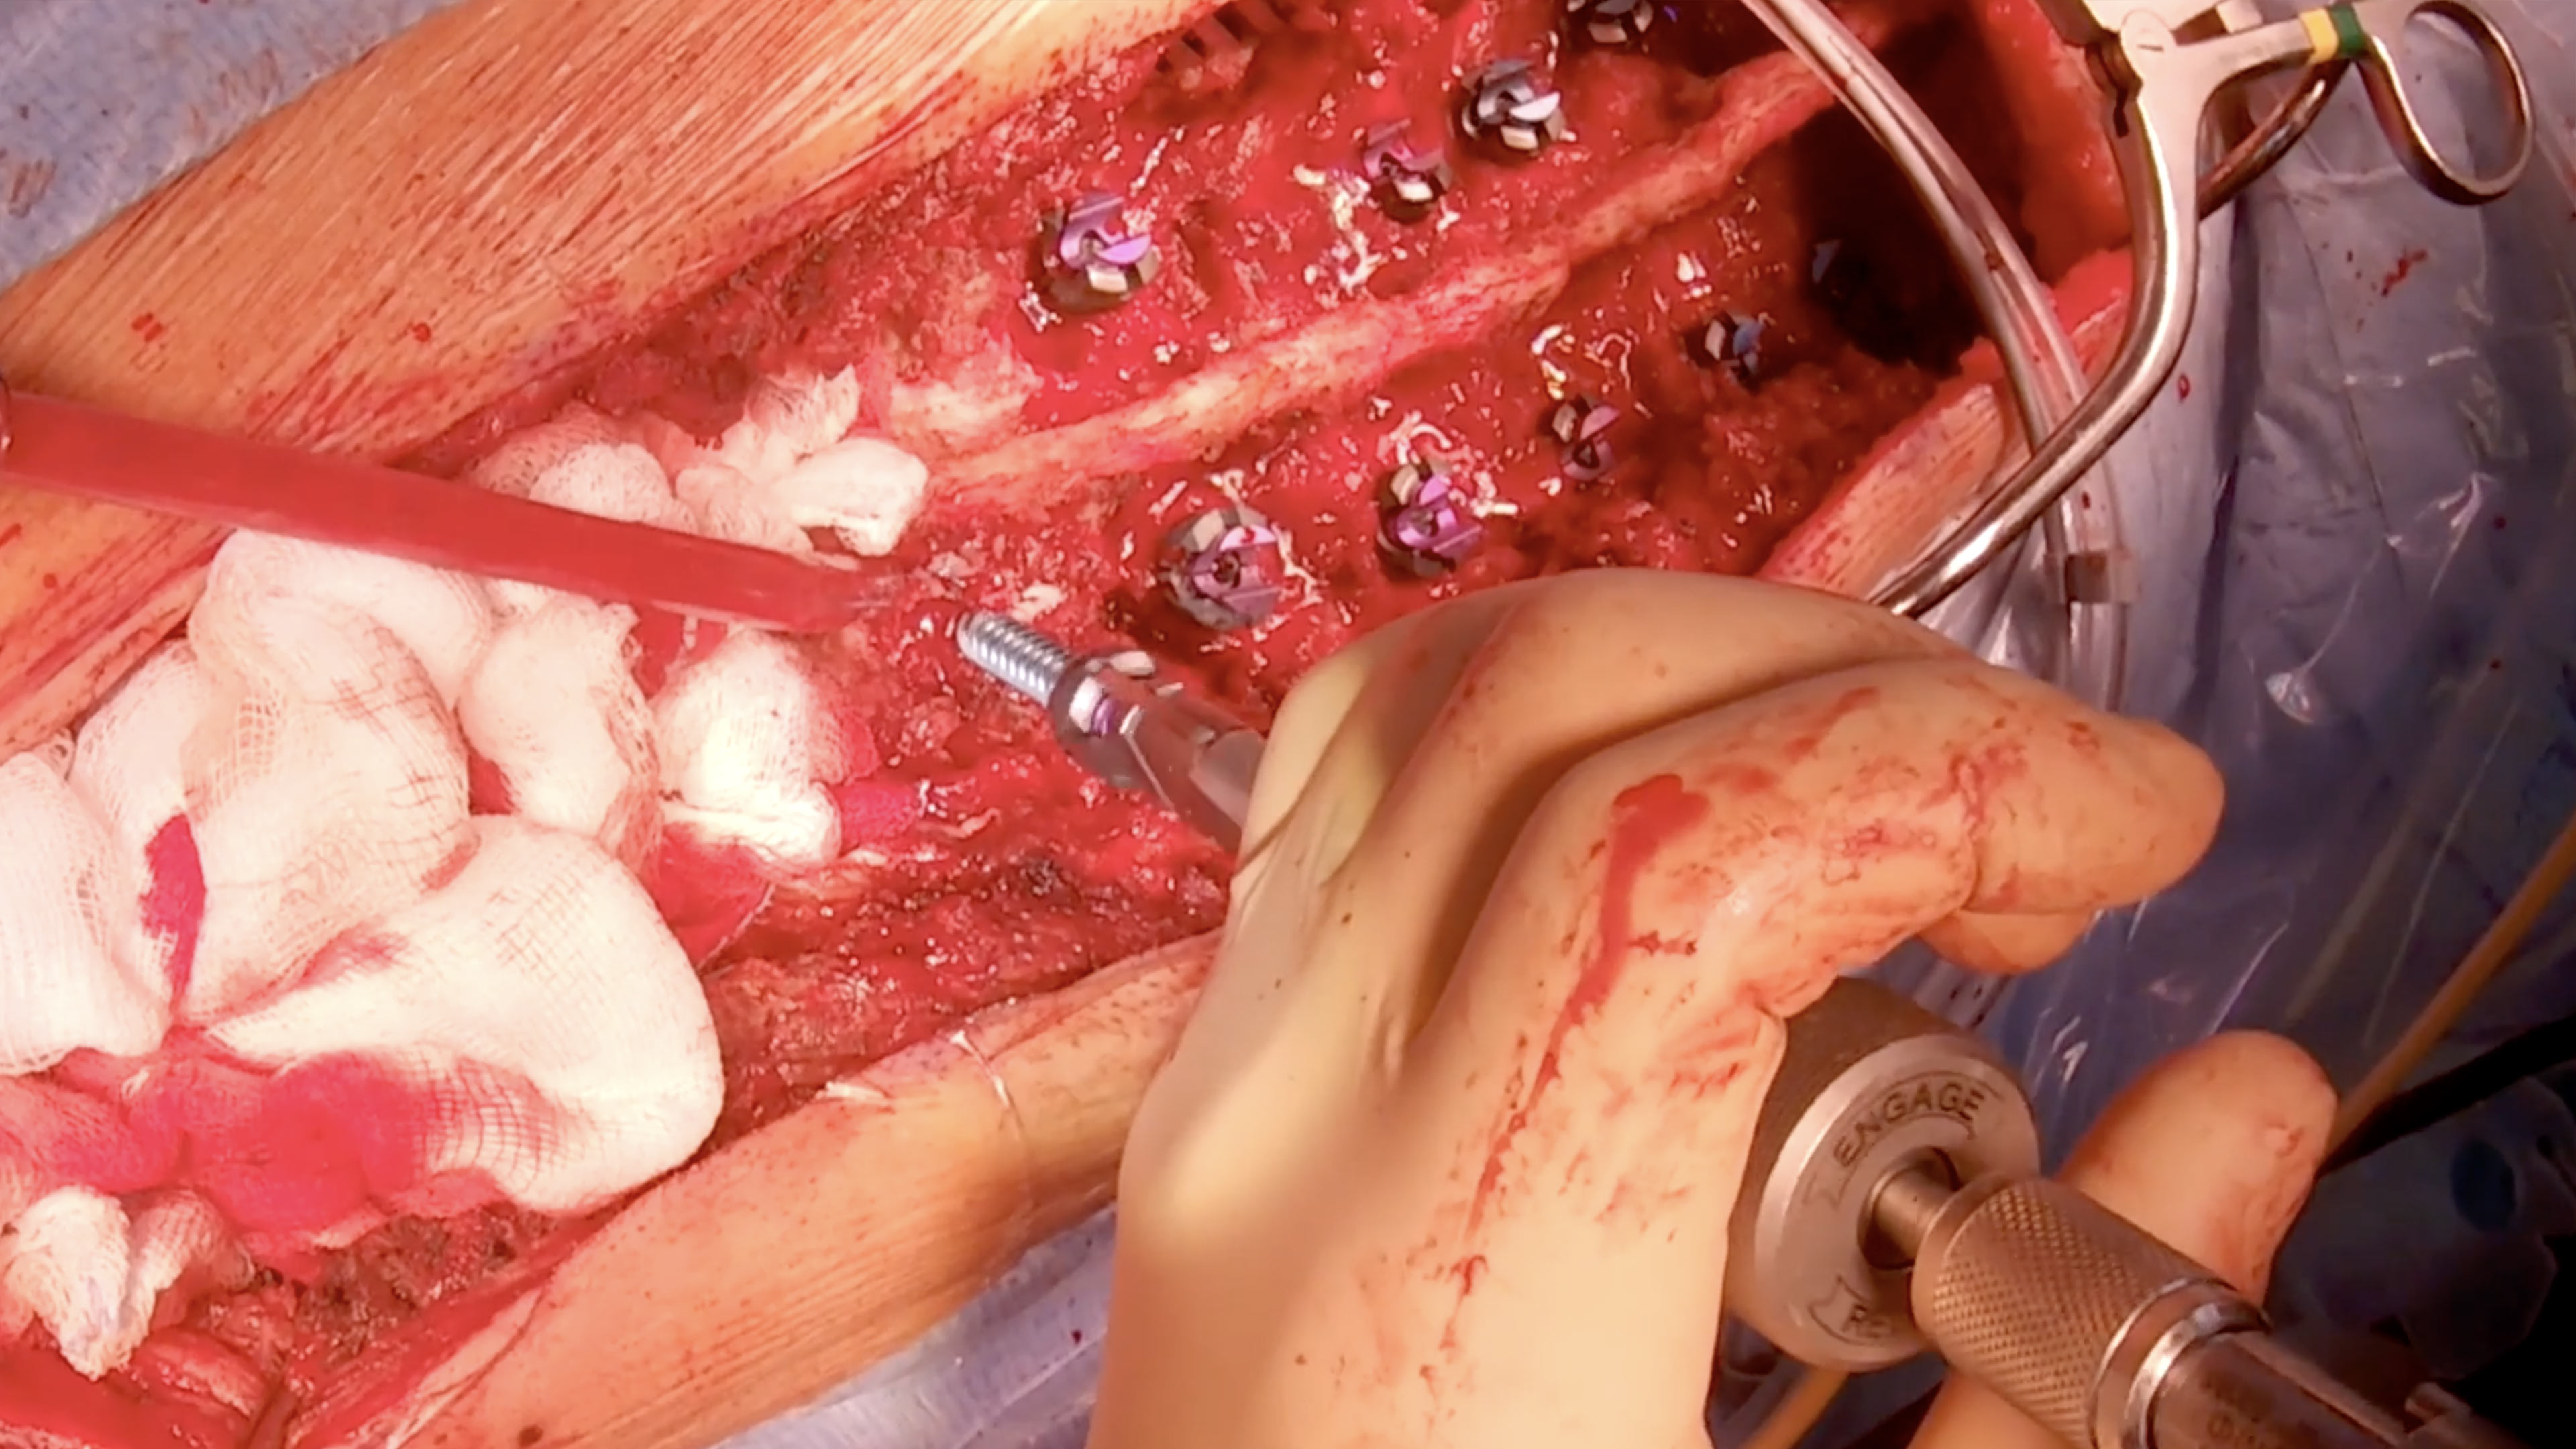

• Severe Deformity in Osteogenesis Imperfecta (Briddle Bone Disease)

Severe Deformity in Osteogenesis Imperfecta (Briddle Bone Disease)

Surgeons:

Antaranyan Ara MD

Koloyan Zaven MD

Aebi Max MD

Wigmore Women's and Children's Hospital

Department of Paediatric Orthopaedics

Yerevan, Armenia

Project 24-011

OOT presents a complex case of osteogenesis imperfecta (OI) i...